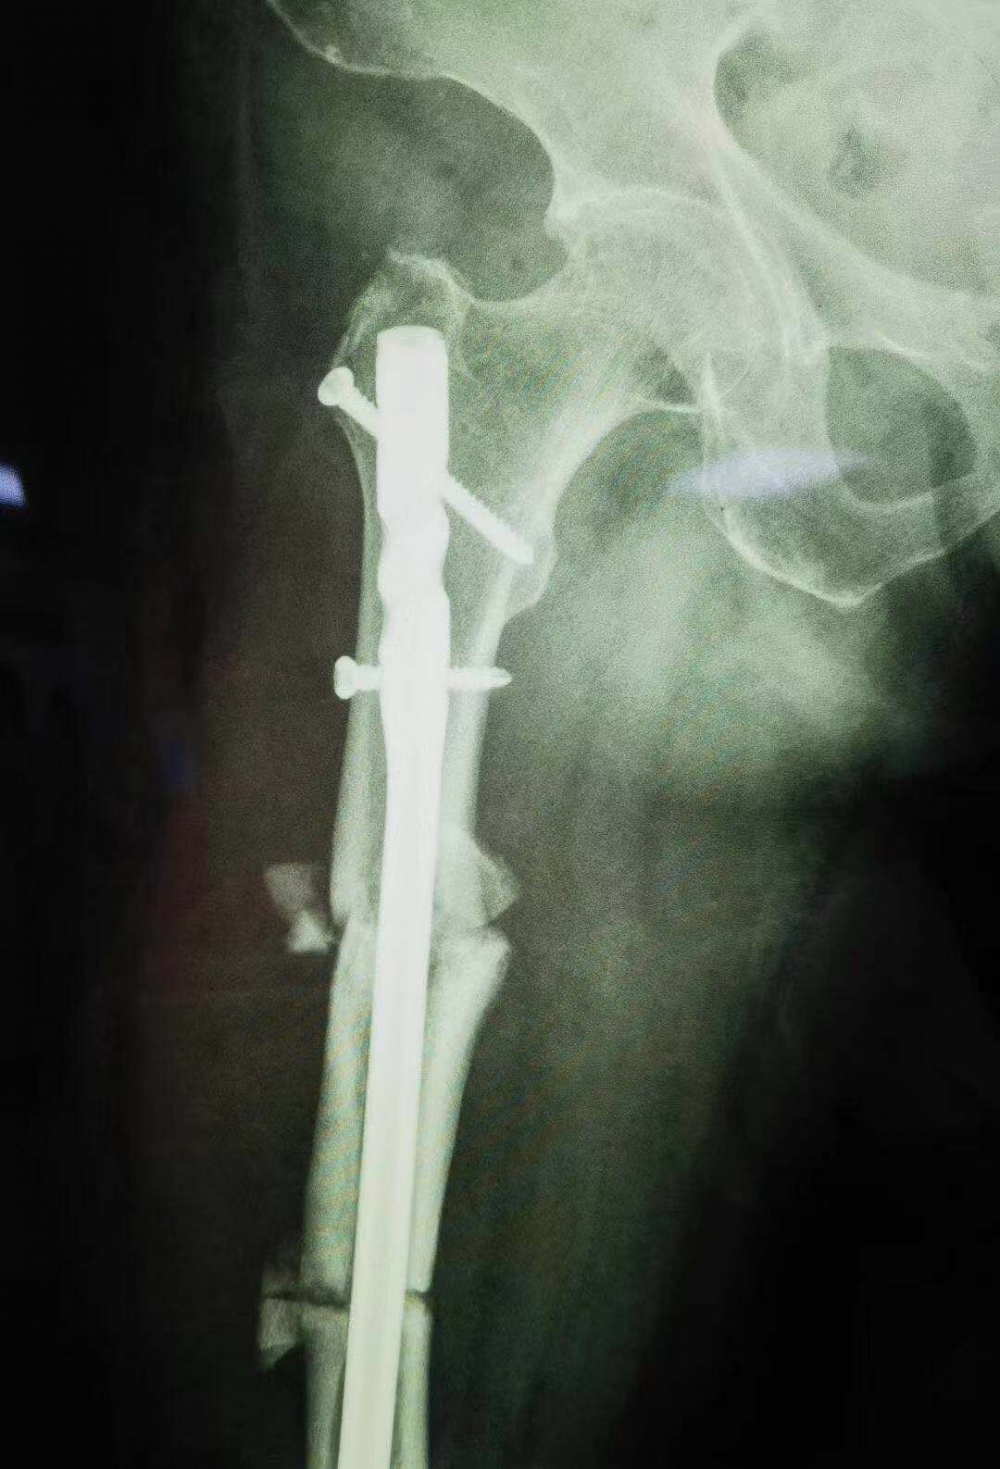

骨伤一科主任汪永泉带领团队多次会诊,拿出较为可行的三套方案,对每套方案进行细致详尽的评估。最终在取得家属同意的情况下,确定在7月28日,由骨伤一科主任汪永泉、管床医生樊炜联合为患者进行手术。

据汪永泉主任介绍,此次手术很成功,术后通过观察,病人目前没有血管的危象,而且整个神经没有牵拉,而且病人整个下肢体长度,也基本达到术前预想的恢复长度。